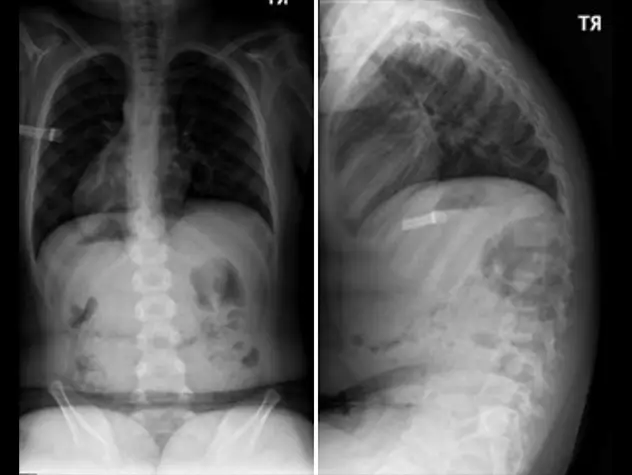

Our pediatric orthopedic specialists from Columbia are among the top in the country, offering specialized expertise in surgical and non-surgical treatments. Renowned for their expertise in congenital, neuromuscular, and traumatic disorders, clinicians and surgeons at the Children's Hospital of New York are also seasoned researchers, seeking to make surgeries safer while optimizing functional and mobility outcomes.

Pediatric Orthopedics